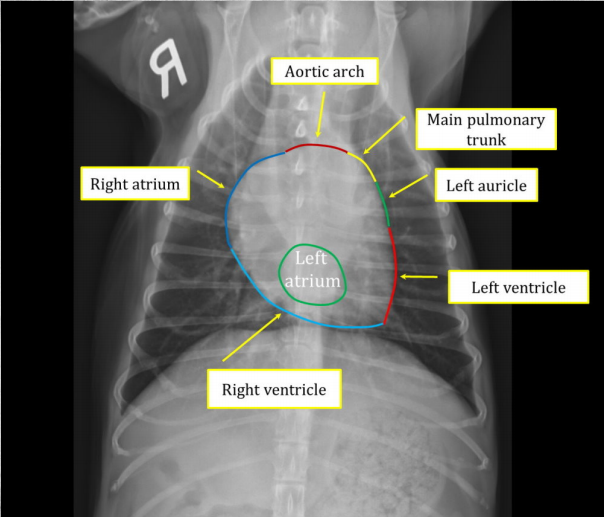

Cardiac silhouettes in dogs. (4)

● "Size is considered normal if no clear abnormalities are seen." ● Distance between base and apex is ca 70% of depth of thorax on lateral view. ● Heart width on LAT view may be 2,5-3,5 intercostal spaces. ● Heart width on VD/DV should not be more than 2/3 of the width of the thorax.

What is VHS?

"vertebral heart size/score" is A way to objectively evaluate cardiac size among dogs of different breeds. ● Long and short axis of the heart is measured on LAT view, length is compared to vertebral length, and a summation is made which gives you a score. ● Actually, No evidence that it is more effective than subjective evaluation by eye. ● Breeds are different! e.g. Bulldogs! (score ref. intervals vary by breed)

VHS, "vertebral heart size/score" To evaluate heart size objectively.